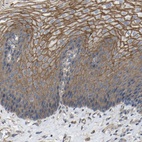

Immunohistochemical staining of human esophagus shows strong membranous positivity in squamous epithelial cells.